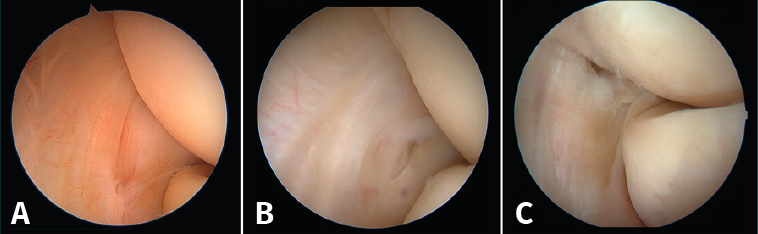

Clasificación de los hallazgos artroscópicos de Baker et al.(29)

Figura 10. La clasificación de Baker de los hallazgos artroscópicos en la tendinopatía lateral del codo. A: tipo I, cápsula lisa sin irregularidades, inflamación y erosión en el tendón del músculo extensor carpi radialis brevis (ECRB), sin muestras de desgarro completo; B: tipo II, desgarros lineales o longitudinales en la cápsula por dentro de la superficie del origen del ECRB; C: tipo III, lesión y retracción capsular con avulsión parcial o total del tendón.

Baker et al.(29) describen 3 tipos de lesiones macroscópicas identificables mediante artroscopia exploradora de codo en los pacientes con epicondilitis (Figura 10):

- Tipo I: cápsula lisa sin irregularidades, inflamación y erosión en el tendón del músculo ECRB, sin muestras de desgarro completo.

- Tipo II: desgarros lineales o longitudinales en la cápsula por dentro de la superficie del origen del ECRB.

- Tipo III: lesión y retracción capsular con avulsión parcial o total del tendón del ECRB.

Aunque esta clasificación puede resultar útil a la hora de describir los cambios patológicos en la articulación, su valor pronóstico es limitado(30).